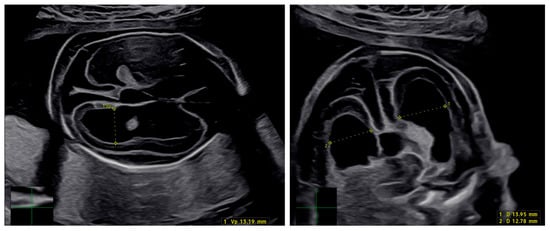

Antenatal Imaging and Neonatal Outcome in Infants with Congenital Cytomegalovirus Infection: The Effect of Valaciclovir

by Francesca Arcieri, Adele Vasta, Sara Sorrenti, Gregorio Volpe, Valentina D’Ambrosio, Daniele Di Mascio, Fabio Natale, Lucia Manganaro, Giuseppina Liuzzi, Maria Caterina Corigliano, Sara Bertolini, Stella Borza, Carla Camerino, Giuseppe Rizzo and Antonella Giancotti

J. Clin. Med. 2026, 15(2), 809; https://doi.org/10.3390/jcm15020809 - 19 Jan 2026

Background: Congenital cytomegalovirus (cCMV) infection is a leading cause of neonatal morbidity. This retrospective study aimed to evaluate the efficacy of valacyclovir in reducing vertical transmission after primary maternal CMV infection and to assess the diagnostic performance of amniocentesis and prenatal imaging. Methods: Eighty-two pregnant women with confirmed primary CMV infection were included. Maternal CMV serology and viral DNA were assessed in blood and urine, with standardized prenatal care including serial ultrasound examinations and fetal MRI when indicated. Amniocentesis was offered to confirm fetal infection. Valacyclovir (8 g/day) was administered before 24 weeks’ gestation, and neonatal infection was diagnosed by CMV DNA detection in urine at birth. Statistical analyses were performed using SPSS version 27.0. Results: Most infections (62.2%) were diagnosed in the first trimester. Valacyclovir was administered in 97.6% of cases, and amniocentesis was performed in 81.7%, with CMV DNA detected in 19.4%. Among 74 live births, 23% of neonates were CMV-positive and 6.8% symptomatic. Seven infected neonates had negative amniocentesis (false-negative rate, 13.2%). Prenatal ultrasound and MRI failed to detect abnormalities in symptomatic cases. Conclusions: Valacyclovir may reduce, but does not eliminate, the risk of cCMV transmission. Negative amniocentesis does not fully exclude fetal infection, highlighting postnatal follow-up. Full article